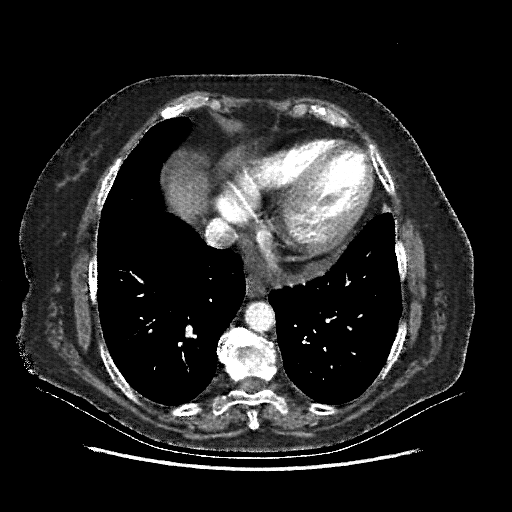

Generated VENOUS CT scan (A→B translation)

Full window (WL 1023.5, WW 4095 β†’ Low βˆ’1024, High +3071)

Original VENOUS CT scan